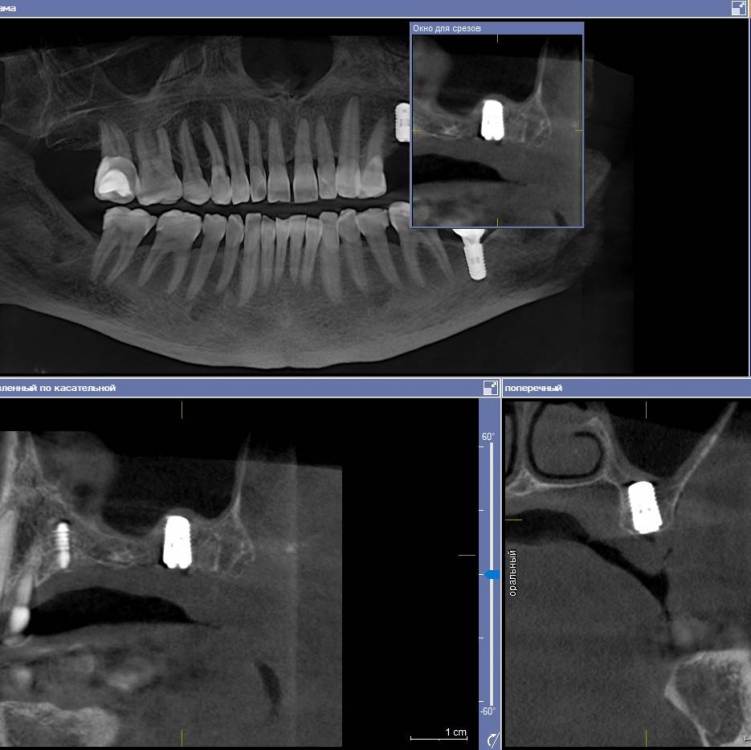

Ponchik Опубликовано 28 апреля, 2021 Поделиться Опубликовано 28 апреля, 2021 Добрый день. Показываю мой новый опыт ? для многих на форуме это рутина, но может кому-то интересно(полезно) будет. 1. Сделано КЛКТ, в GalileosViewer примерное планирование из расчёта избежать синуслифтинг (очень против пациентка). 3.7 на КТ моя работа два года назад. Выявлен новый кариес на дистальной у 3.6. 2. Сделал скан на primescan 3. Планирование далее в другой лаборатории. Наш техник пока не смог в 3д принтер (Надо самому освоить) Пришлось долго переписываться. Так как в дайкомоских файлах нет оказывается плана на имплантацию. Он не передаётся. 4. Изготовили и доставили шаблон. 5. Итоговая работа - 2.5 - штрауманн бл 4.1-8 2.7 - штрауманн бл 4.8-8 с небольшим поднятием остеотомом дна. Поднимал даже не стуча, продавилось остеотомом. Замечания: шаблон сел хорошо, особенно когда отломились резцы ))). Обговорить поперечные балки с техником я не догадался и на резцах шаблон и заканчивался. Дистальная часть заметно двигалась вверх, вниз. Вставить фрезу с надетым шаблоном, нереально в области 2.7, 2.8. рот так не открывается (эх, был бы это Мик Джагер) попробовал втавить фрезу в шаблон, а потом наконечник прищёлкнуть, не смог. Всё равно не влезть. поэтому дистальная втулка использовалась как направляющая для грифеля карандаша. Ну хоть так шаблон, но помог. Передняя втулка довольно легко выдвигалась. Не подклеивал ни как. Вывод: не смотря на неудобства, считаю шаблон мне очень помог. Учитывая огромную толщину слизистой и хз как я бы там на глаз наставил. А так даже без вертикальных разрезов работал. 3 2 Ссылка на комментарий